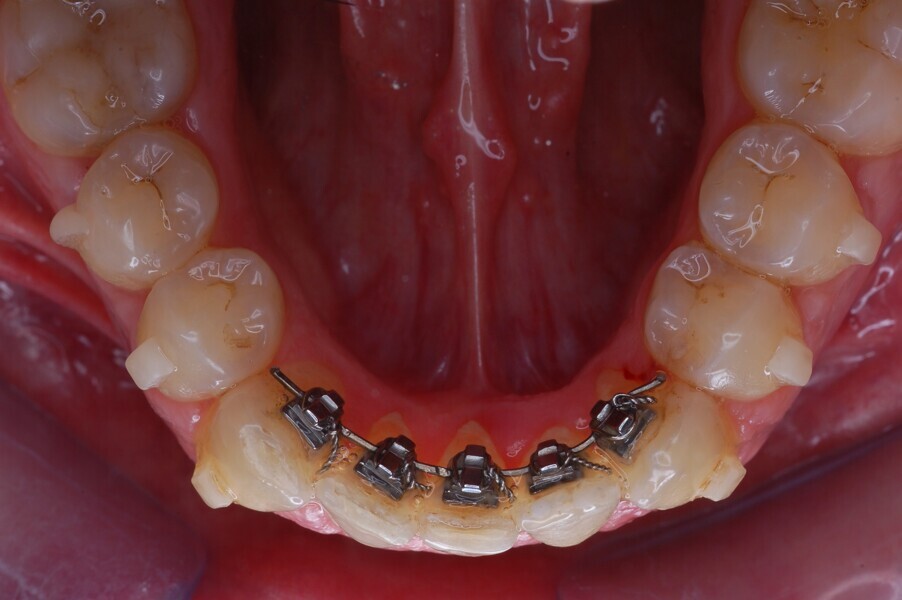

Fig. 37–44: Sequential intra-oral photographs illustrating progressive alignment of the mandibular arch.

Fig. 38.

Fig. 39.

Fig. 40.

Fig. 41.

Fig. 42.

Fig. 43.

Fig. 44.